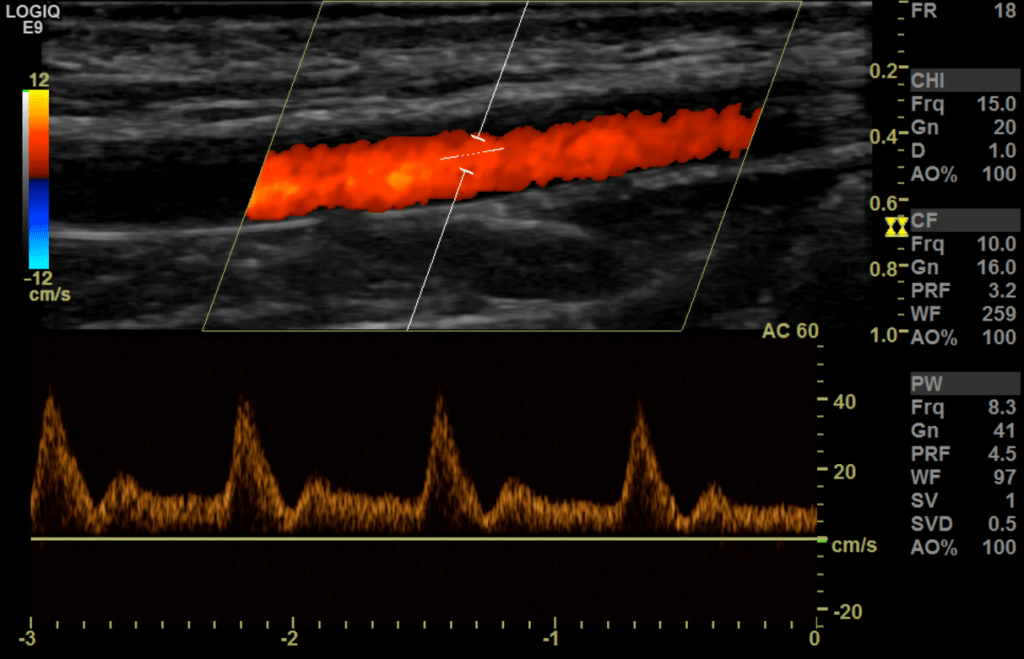

Fistula waveform

A fistula waveform is going to be high velocity, low resistance in both the artery and the vein. It is often turbulent with spectral broadening. The further away from the anastomosis you go the lower the pulsatility gets.

In normally functioning fistulas, waveforms of flow in the supply arteries and throughout the graft are monophasic, with peak systolic velocities of 100-400 cm/sec and end-diastolic velocities of 60-200 cm/s (stenosis at the anastomosis sight is common and has been determined to not adversely effect graft/fistula function and no association between stenosis and graft occlusion has been found.

sec. The draining veins have arterial pulsations with peak velocities of

30-100 cm/sec.

In this case the radial artery is the inflow; and the forearm cephalic vein the outflow.

We begin our exam protocol by evaluating the inflow stream proximal to the anastomosis beginning with the subclavian artery followed by the axillary, brachial, ulnar and radial.

The normal spectral arterial tracing (inflow) proximal to the AVF will be a lower resistant high flow waveform followed by a higher resistance waveform distal to the anastomosis (make sure to evaluate for steal syndrome). The spectral analysis in the radial artery proximal to anastomosis has a high PSV/EDV at 247 cm/s and EDV at 119 cm/s.